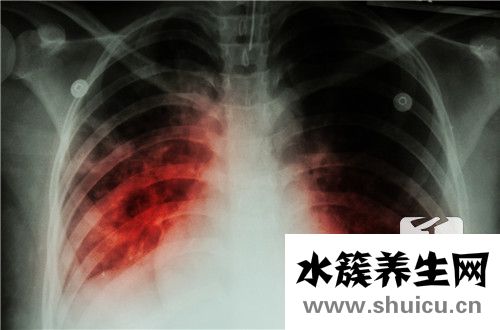

?右肺鈣化是肝實質(zhì)肺細(xì)胞炎癥的陰影,通常與肝膽結(jié)石有關(guān),并且肺血管陰影和結(jié)核鈣化的發(fā)生也可引起肺鈣化,因此應(yīng)及時治療患者。 不會傳染,可以通過組織修復(fù)來改善。 對于右肺鈣化的癥狀,您可以了解以...